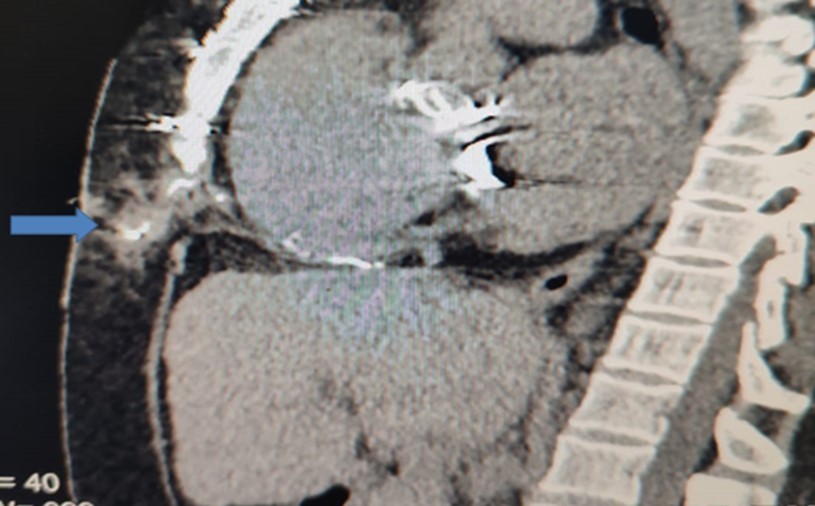

After weaning from cardiopulmonary bypass, as per institutional protocol for heart-valve operations, right atrial and /or right ventricular epicardial and diaphragmatic pacing wires (Quad Polar, 250 cm, Medical Concepts Europe (MCE), MCE Gemert, Netherlands) were inserted. Atrial wires were fixed with 5/0 prolene sutures taking superficial bites on the surface of the epicardial surface layer just to ensure gentle contact with the heart muscles and minimize complication rate 3, 5. The exit site in the epigastrium to the right of the midline was secured with a 2/0 silk suture. After an uneventful recovery in intensive care, each patient was transferred to the ward. As per institutional protocol, all postoperative cardiac surgical patients receive low molecular weight heparin subcutaneously as a prophylaxis against deep vein thrombosis The DVT-prophylaxis is continued until the day of discharge or when the patient is fully ambulatory. We do not stop the prophylaxis before temporary Pacemaker Wire-removal. On the 4th postoperative day, the pacing wires were pulled out with gentle traction. In centers other than ours, some surgeons only excise the external portion of the wires. This was complicated with chronic abscess and sinus formation years after surgery (Table 1). Diagnosis was confirmed radio-logically (Figure 1).

Figure 1.Sagittal CT-section of chest showing the extension of the sinus track containing the contrast

Sagittal CT-section of chest showing the extension of the sinus track             containing the contrast

b) Computerized tomography with mild push of contrast to the sinus track (Figure 1)